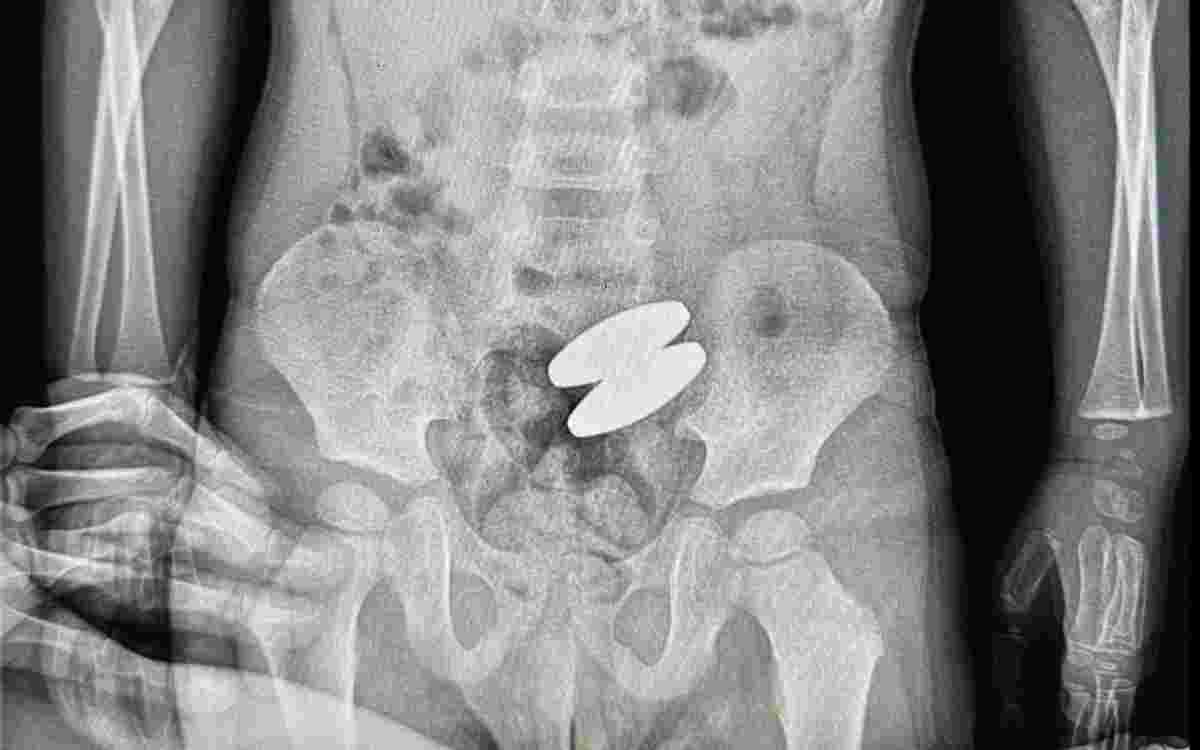

«Я перевірила батарейки в іграшках та інші деталі. В лікарні у Володимирі, куди ми звернулися спочатку, я наголосила, що підозрюю проковтування стороннього предмету. Зробили рентген і вже тоді я побачила магніти з холодильника, якими ми прикріплювали записки, календарі», – розповіла жінка.

Хірург Василь Никитюк, який лапаросокопічно прооперував хлопчика, наголосив, що ці магніти великі й важкі, тож природньо б не вийшли. На момент операції магніти були з’єднані між собою, тисли на стінки кишківника, внаслідок чого у цих ділянках припинилося кровопостачання – без оперативного втручання це загрожувало перфорацією. Нині дитина почувається добре.